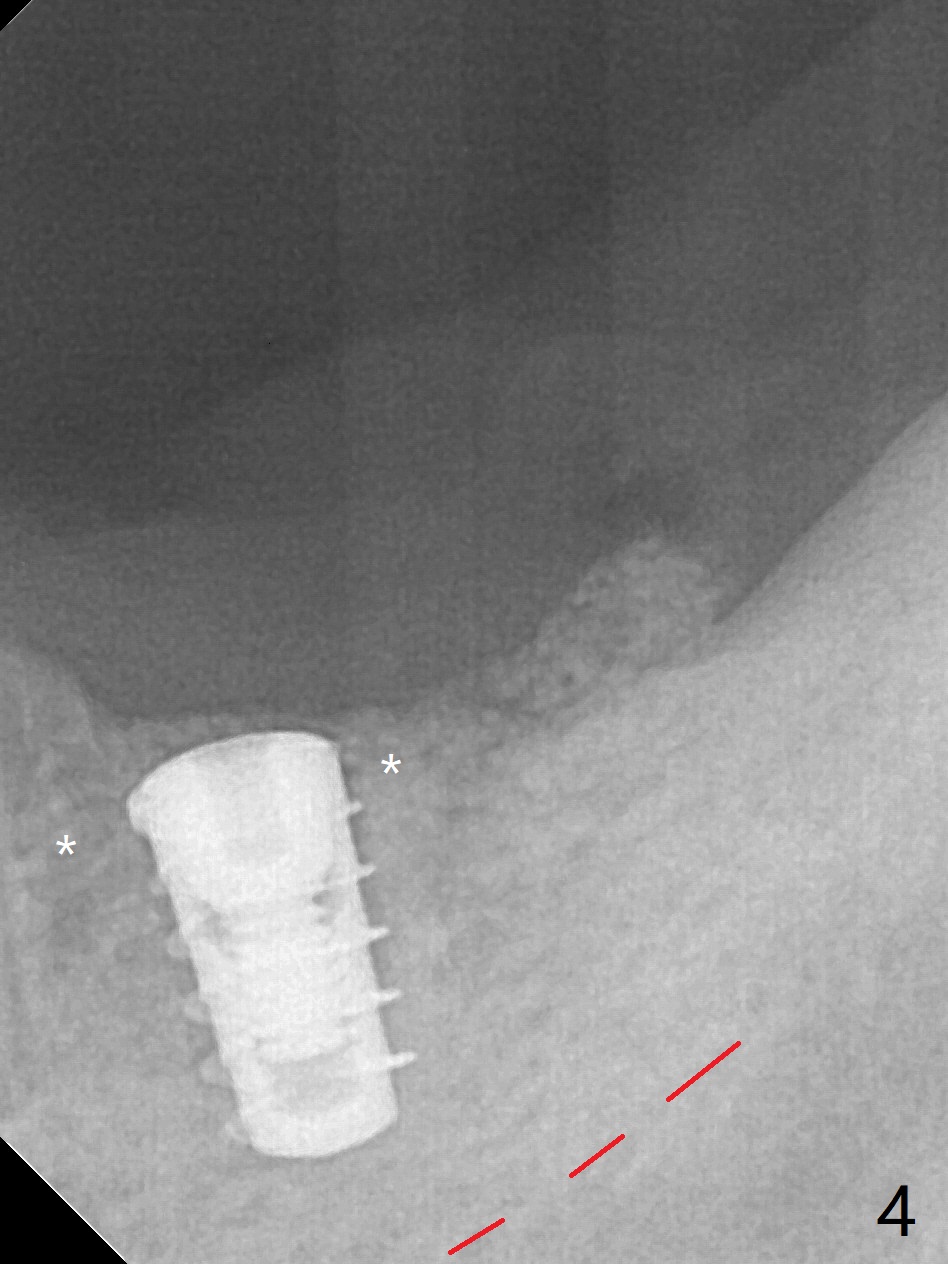

After use of 4x7.3 mm drill with guide, the buccal osteotomy height is 4 mm at #19, unsuitable for 4x5 mm Bicon implant, which requires 3 mm subcrestal placement. PA shows 4.3 mm bone from the Inferior Alveolar Canal (IAC, red dashed line (the superior border)). Following 4x8.5 mm drill, a 4x7 mm IBS implant is placed with distobuccal thread exposure and 3.2 mm clearance from IAC. With 3.5x10 mm drill less full length, the implant is placed a little deeper (10 Ncm). Bleeding spots created (Fig.3), sticky bone (cortical, fine granule) is placed (Fig.4 *), which is covered with PRF membrane and Colla tape. 4-0 PGA is used. There is no postop paresthesia. The length discrepancy is probably due to distal free end guide, which produces mesial placement of the implant. Try to make a premolar-sized crown. Use profile drill in uncover.